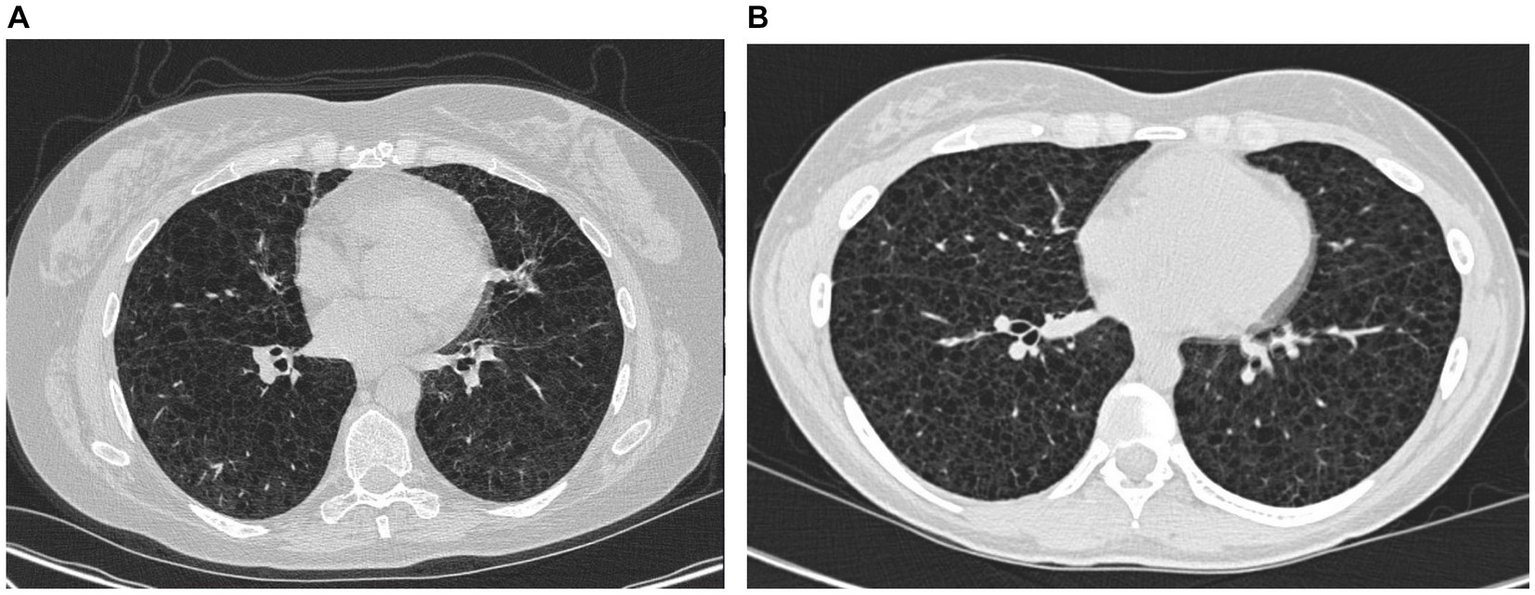

Figure 3

High-resolution computed tomography from case 1 (A) and case 2 (B).

In February 2023, the patient experienced increasing breathlessness and was referred to an HRCT by the Oncology Department based on suspicion of treatment-induced pneumonitis due to ongoing treatment with pazopanib. The HRCT showed similar findings as before but this time interpreted as cysts and not emphysematous bullae (Figure 3A). In a multidisciplinary team discussion with thoracic radiologists and pulmonologists, the findings were found to be compatible with LAM. She was referred to the Center for Rare Lung Diseases at the Department of Respiratory Diseases and Allergy, where pathology re-evaluation of the retroperitoneal tumor was performed. It was initially evaluated as a leiomyoma with a predominance of smooth muscle cells. Upon second opinion, immunohistochemistry was highly positive for microphthalmia-associated transcription factor (MITF), muscle-specific actin, and human melanoma black 45 (HMB45) and negative for Melan-A, thus supporting a diagnosis of LAM. Later, the LAM diagnosis was supported by an elevated VEGF-D (Figure 1). She showed no other intra-abdominal features of LAM. Treatment with pazopanib was discontinued and treatment with sirolimus was initiated, supplemented by leukotriene antagonist and combined ICS/LABA/long-acting anticholinergics. Pulmonary function tests showed severe obstructive reduction and a low diffusion capacity for carbon monoxide (DLCO) (Figure 1). After 6 months of treatment with sirolimus, MRI showed no change in the size of the lymphangioleiomyoma.

The course of the disease is outlined in Figure 4. The second case describes a woman, who at the age of 16 was suspected of exercise-induced asthma, but the symptoms subsided without treatment. At age 29, she was diagnosed and treated for asthma at a private clinic. She was a non-smoker with no history of pregnancies or hormone therapy. Because she had had no clinical benefit from her asthma therapy, at age 32, she was referred to the Center for Rare Lung Diseases at the Department of Respiratory Diseases and Allergy in 2015. There, PFTs showed severe obstruction and DLCO reduction (Figure 4). An HRCT was performed showing multiple cysts compatible with LAM (Figure 3B). Cell differential count by bronchoalveolar lavage was normal, but a transbronchial biopsy showed a slight thickening of the alveolar septae with spindle-formed cells. By immunohistochemistry, these cells were positive for smooth muscle α-actin, muscle-specific actin, and estrogen receptors, and negative for Melan-A, thus compatible both morphologically and by immunohistochemistry with LAM. Later, a VEGF-D of 3,505 pg/mL supported the LAM diagnosis. Treatment with sirolimus was initiated. As indicated in Figure 4, her lung function has been stable since the initiation of the treatment. Due to skin changes, she was investigated for TSC at the Clinical Genetics Department, but this was disconfirmed.